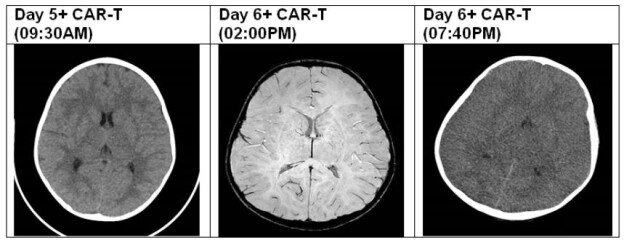

We report a case of a 4-year-old boy, with B-cell precursor acute lymphoblastic leukemia (ALL) with CNS involvement. Due to high risk relapse/refractory disease he was enrolled on a clinical trial using CD19 CAR T-cells. The patient developed CRS on day +3 (grade 1), and due to encephalopathy, high fever and seizures he was transferred to pediatric intensive care (PICU) on day 5 of CAR-T treatment. Prior to transfer to PICU, due to a clinical diagnosis of ICANS grade 3, he was commenced on dexamethasone, on top of Levetiracetam prophylaxis (started on day -3). Following this event, a brain CT was performed and was normal, showing no intracranial bleeding or oedema. EEG revealed general encephalopathy. Following repeated tonic-clonic seizures despite increase in the Levetiracetam dose and steroids treatment, he was loaded with phenytoin as well as a few midazolam boluses to stop the seizures. During the first 24 hours in PICU, the patient remained stable, encephalopathic, however maintained GCS of 8-10. The following day (+6) a brain MRI was performed under general anesthesia, showing high T2-FLAIR signal involving the hemispheral sub-cortical white matter, hippocampi and capsule externa, in addition to high signal in the thalami bilateral. Furthermore, there were cortical areas with diffusion strain which correlate with ICANS. The patient was extubated and returned to PICU drowsy but responsive. Upon returning from MRI the patient had a sudden acute deterioration, with apneic episode and GCS which dropped to 3, therefore was immediately intubated. An urgent repeat CT brain was performed revealing diffused brain oedema with developing herniation of cerebellar tonsils (Figure 1). During the next 24 hours he received mannitol, hypertonic saline, and noradrenaline to maintain proper cerebral perfusion pressure and reduction of oedema, he was started on broad spectrum antibiotics and anti-viral empiric therapy for possible meningo-encephalitis, as well as pulse methylprednisolone and tocilizumab. Unfortunately, the patient showed no neurological improvement and had absent brain stem reflexes and anisocoric pupils. SPECT was performed showing absent flows which correlates with brain death.

Figure 1: CT/MRI findings.